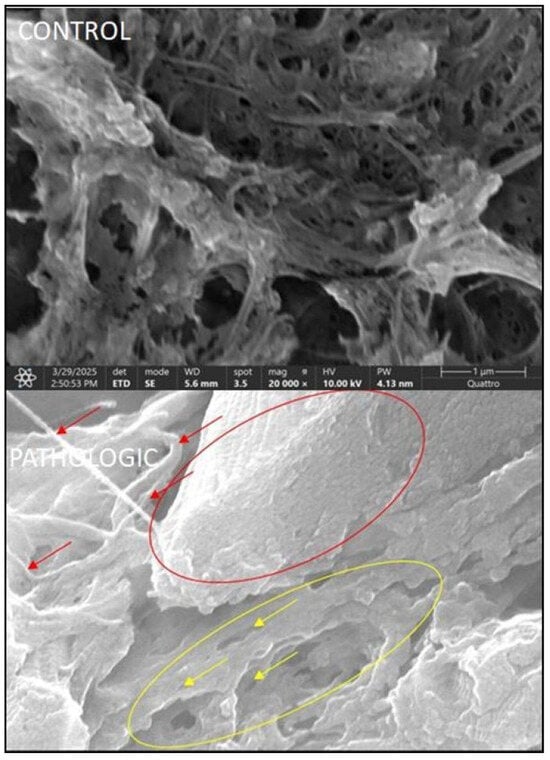

3.3. Results of SEM Study

- The trabecular bone’s appearance, with well-organized trabeculae, is strategically distributed to support mechanical loads;

- The spaces between the trabeculae contain bone marrow or blood vessels.

- Vascular network:

- Small blood vessels (capillaries) that run through the bone, evenly distributed in the Haversian and Volkmann canals (Figure 9, CONTROL);

- The ultrastructural details of the capillary wall show a thin endothelium with mitochondria and elongated nuclei.

- Possible perivascular cells associated with maintaining vascular and metabolic function.

- The collagen fibers and extracellular matrix provide support for blood vessels;

- Osteoprogenitor cells are located near the capillaries;

- The fineness of normal vascularization is highlighted, which emphasizes the intimate relationship between bone and the vascular system, which is essential for bone nutrition and regeneration (Figure 10, control).

- Structural continuity: mean scores are 2.0–2.5, indicating a significant loss of tissue integrity;

- Fibrillar organization: mean scores are 2.5–3.0, reflecting severe collagen disorganization;

- Vascularization: mean scores are 2.0–2.5, with evidence of abnormal vascular networks;

- Comparison of the mean SEM total scores between the pathological group (6.14) and the control (0) reveals a clear and significant difference (p < 0.001).

- Continuity/structural integrity: total score of 102, with an average of 2.0 per patient, which indicates a moderate impairment of the tissue structure;

- Presence of collagen/fibrillar organization: total score of 124, with an average of 2.43, which suggests a significant disorganization of the collagen network;

- Vascularization/visible capillaries: total score of 102, with an average of 2.0 per patient, which reflects the abnormal presence of blood vessels in the analyzed cartilage.